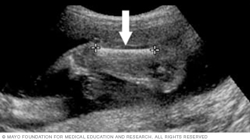

Below is a view of a fetus's head. The thicker white lines that form a circle are the skull. The white line in the middle of the circle is the midline structure that separates the baby's brain into its right and left halves. Head measurements can help determine the age of a fetus.